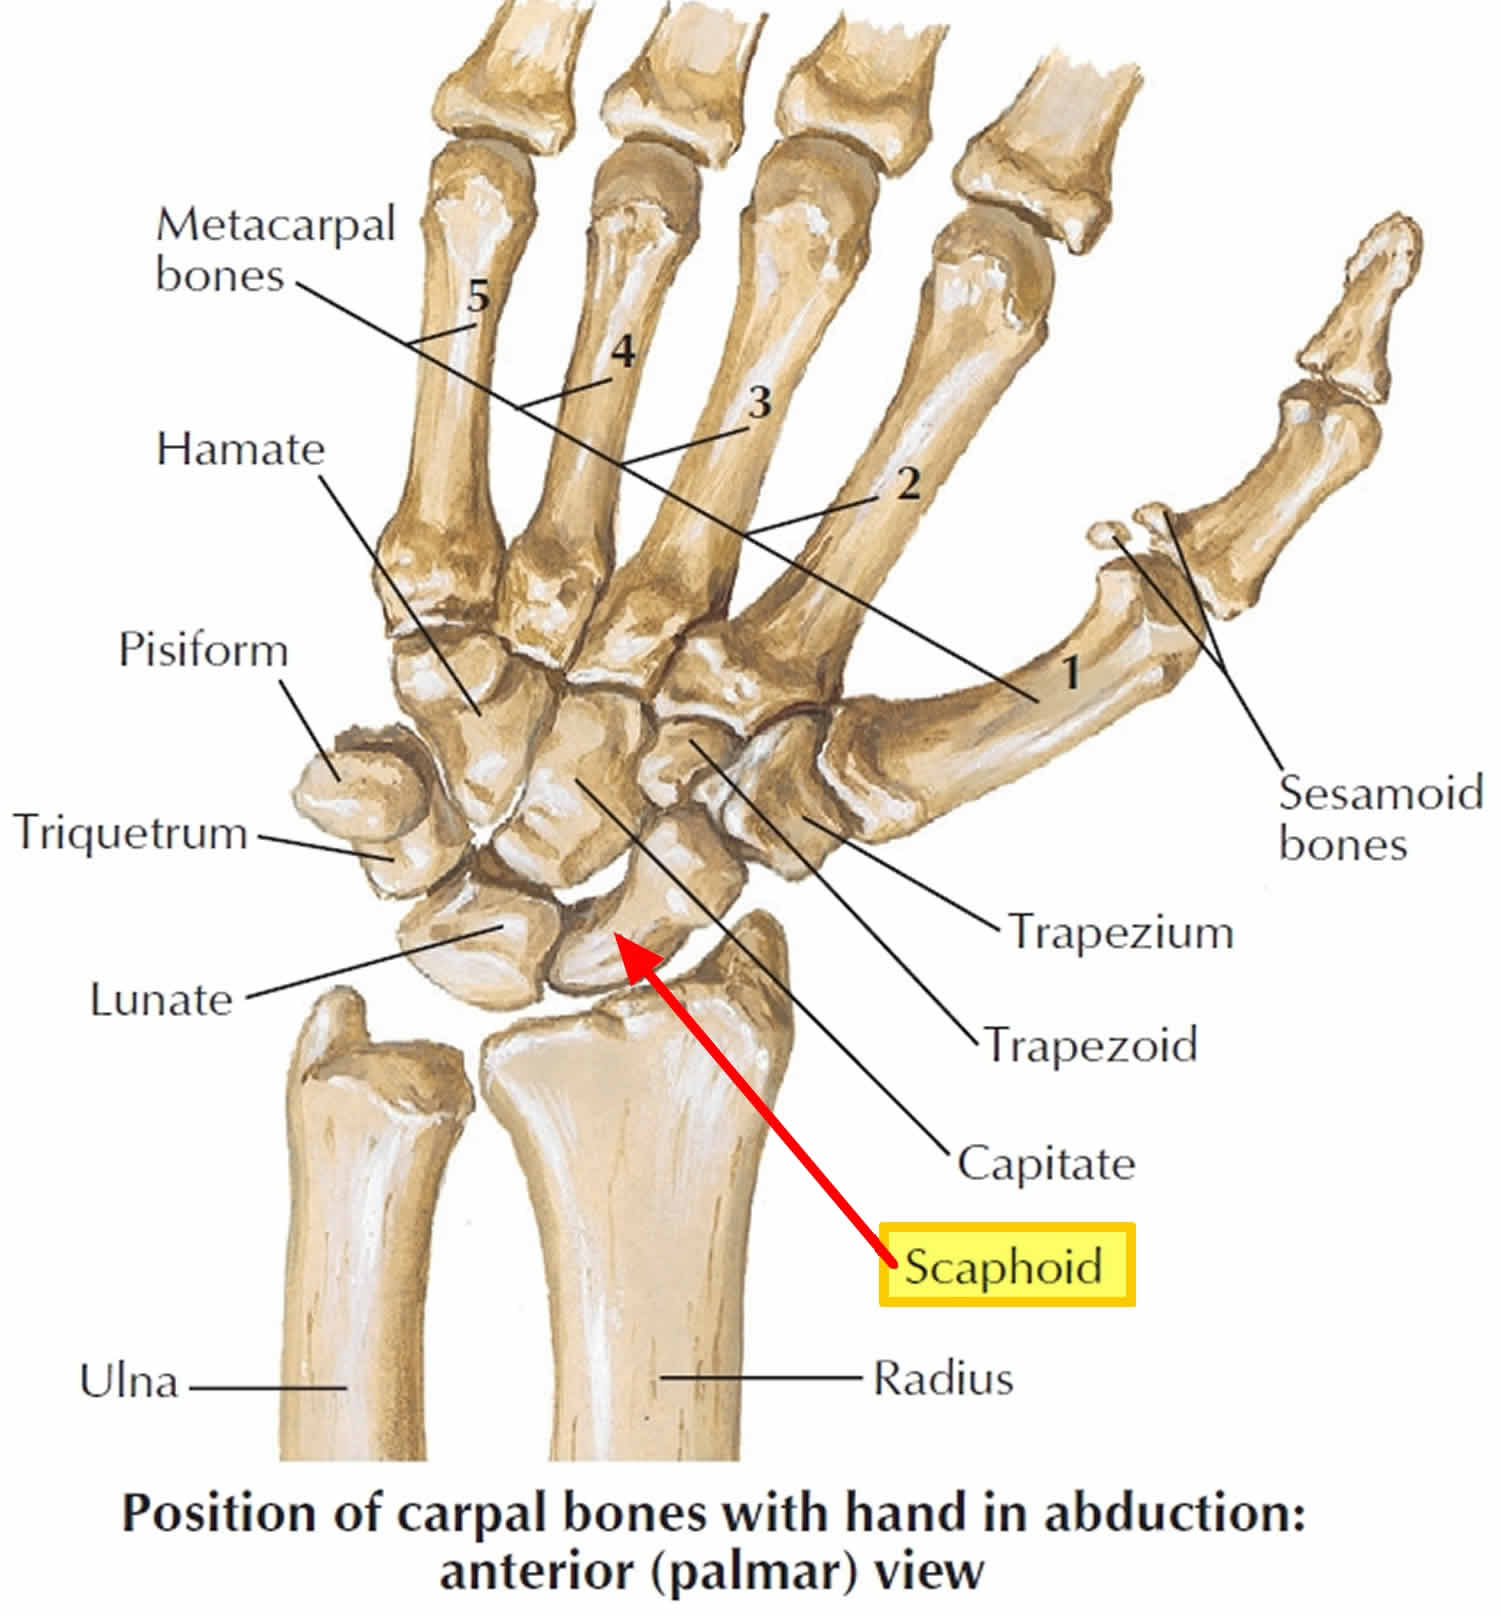

Scaphoid (Navicular) Fractures – Dr. Groh

Scaphoid (Wrist Bone) Fracture – Orthopedic Specialists of Seattle

Scaphoid fracture causes, symptoms, diagnosis, treatment & revovery time

Radiograph of the left wrist shows stress fracture of the left scaphoid …

Scaphoid Fracture Of The Wrist Photograph by Maurizio De Angelis …

Scaphoid Fracture of the Wrist | eOrthopod.com